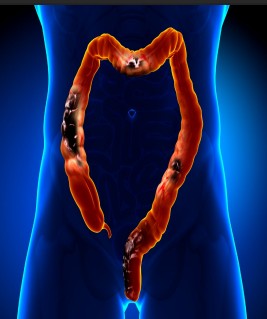

mucosa, IBD, dysplasia, benign, adenomatous, neoplastic

Colon Polyps: Types

-Mass or finger like projection arising from the colonic ______

50, adenocarcinoma

Colorectal Cancer: Background

-Epidemiology → most common in those > __, incidence slowly rising in those 20-54

-Pathology → >90% arise from adenomatous polyps, leading to ____________

Takes 10-15 yrs